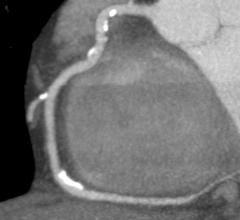

Canon Medical Systems’ offering includes: computed tomography, magnetic resonance, ultrasound, X-ray, cath and EP lab